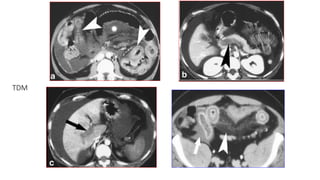

A: Ischémie artériel aigue segmentaire; réduction de calibre et distension intestin

en d’amont

B: Infarcissement veineux; augmenté de calibre, la paroi est épaissie et réduit la

lumière.

Les ischémies veineuses intestino-mésentériques

• L‘IVM: 0,2 à 2% dans séries

autopsies

• L’IVM:

-Aspect "intestin noir"

-La paroi est épaissie

-Réduction de lumière

-Extravasion du plasma

• Etendu et obstructive

TDM